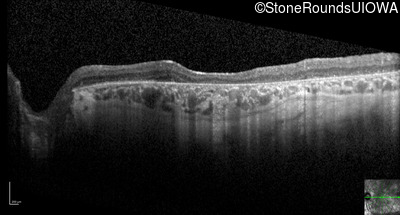

Optical Coherence Tomography - Left - 10/225

Exemplar / OCT Stack